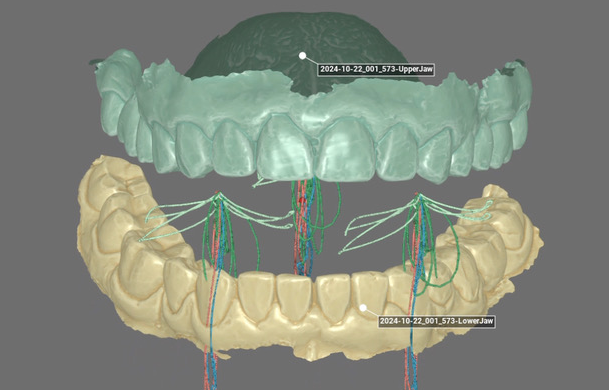

Nei casi di denti mancanti, l’uso degli impianti consente soluzioni altamente funzionali ed esteticamente integrate. Dalla pianificazione protesicamente guidata all’esecuzione, ogni fase viene gestita con attenzione ai tessuti e all’occlusione.

Riabilitazione Implanto-protesica

Soluzioni personalizzate su impianti per ripristinare funzione, comfort ed estetica.

Implantologia

Pianificazione guidata e precisione protesica per riabilitazioni funzionali e naturali anche nei casi complessi.

Analisi della masticazione

Valutazione dinamica dell’occlusione per ottimizzare funzione, comfort e durata delle riabilitazioni.